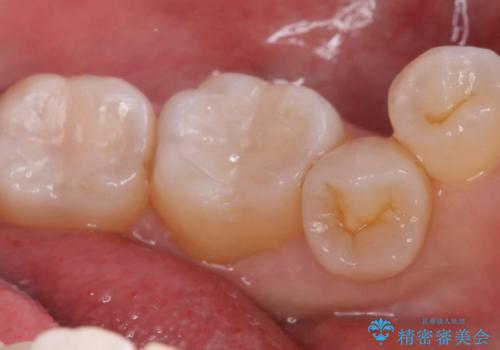

下顎大臼歯部に入っている保険適用のメタルインレーを、適合性と審美性の良いセラミックインレーでのやり替えとなりました。

セラミックインレーセット時はラバーダム防湿を行っています。